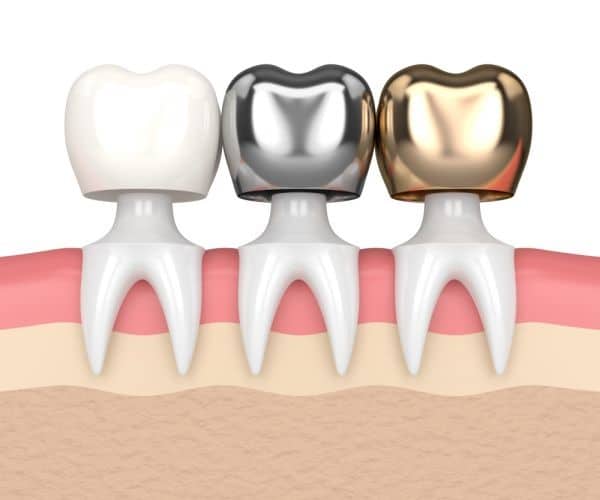

Brush regularly, twice a day for 2 minutes a time. This gives your dentist a more solid. There are different ways to repair teeth, a tooth build up is one way to repair or rebuild a tooth if it has had dental decay or has been broken.

In cases where the tooth has been decayed so badly because of caviti. Use a brush with soft bristles that is small enough to fit into your. Only more recently, dentists use composites in order to create the core buildup because they act through adhesion and require a less invasive preparation.